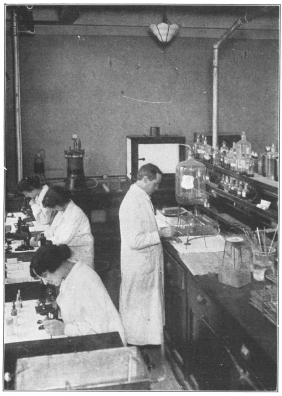

Test for Blood Pressure | 192 |

Indican Test in Urinalysis | 193 |

Microscopic Study of the Blood | 208 |

| 209 | |